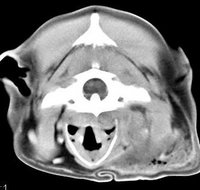

imágenes de TC en el perro | ||||||||||

ejemplo de imágenes de TC en el perro. Nótese la celulitis en la región parotídea izquierda | ||||||||||